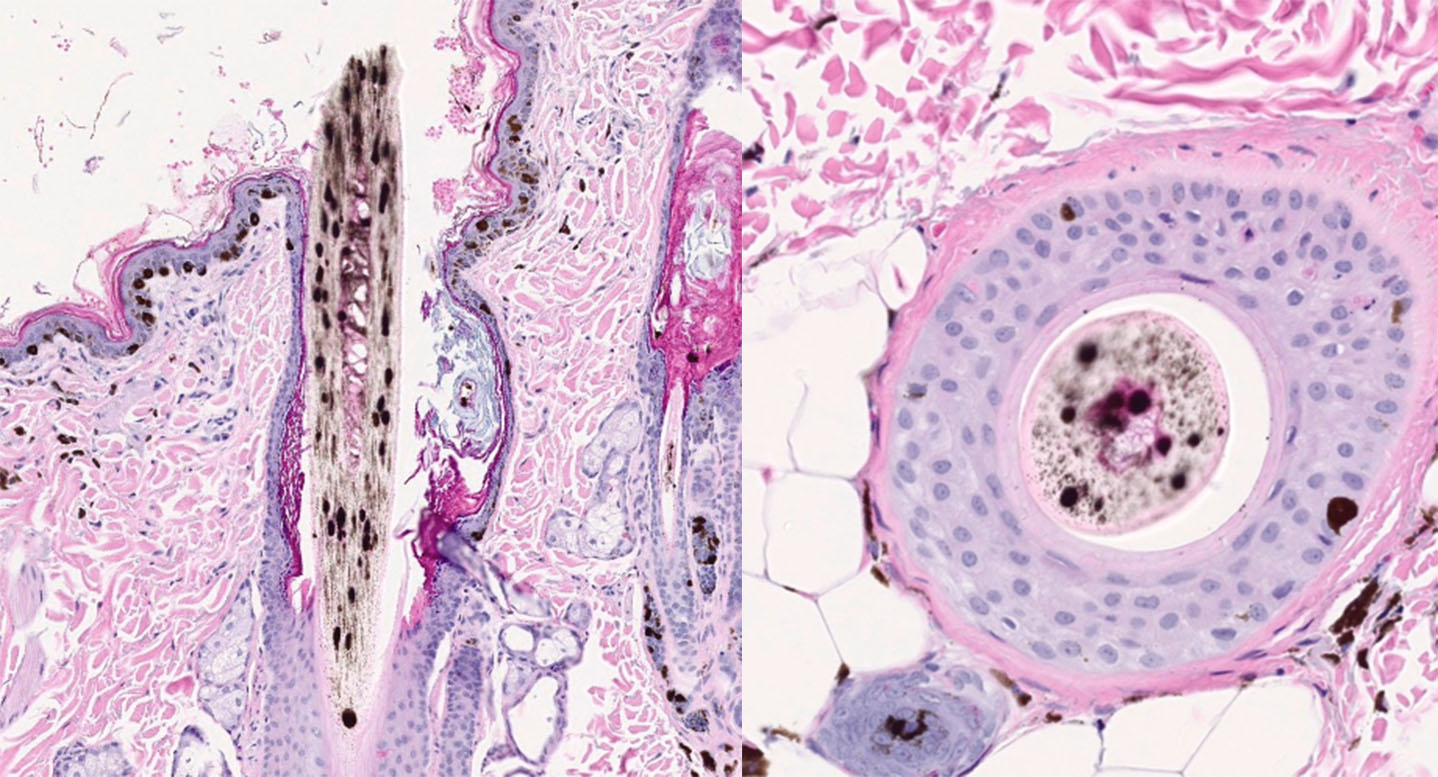

Figure 1. |

An 11-year-old, spayed female, Dachshund with a blue hair coat color presented with widespread, patchy alopecia. The patient began developing partial alopecia ten years prior on the dorsum. Three years later, the alopecia affected the trunk, and the dorsal back was almost bald. There was no pruritus, pustules, or erythema. After an additional three years, the patient developed seborrhea sicca and erythema. Cytopoint therapy was initiated at that time. The alopecia slowly progressed to the entire body. CBC/chemistry were normal. On presentation, there was partial alopecia with mild, flaky skin and hyperpigmentation, especially on the dorsal skin, as well as numerous small (1-2 mm), raised, black comedones.

Figure 2. |

Figure 3. |

Figure 4. H&E, 2x magnification.

Figure 5. H&E, 10x & 20x magnification